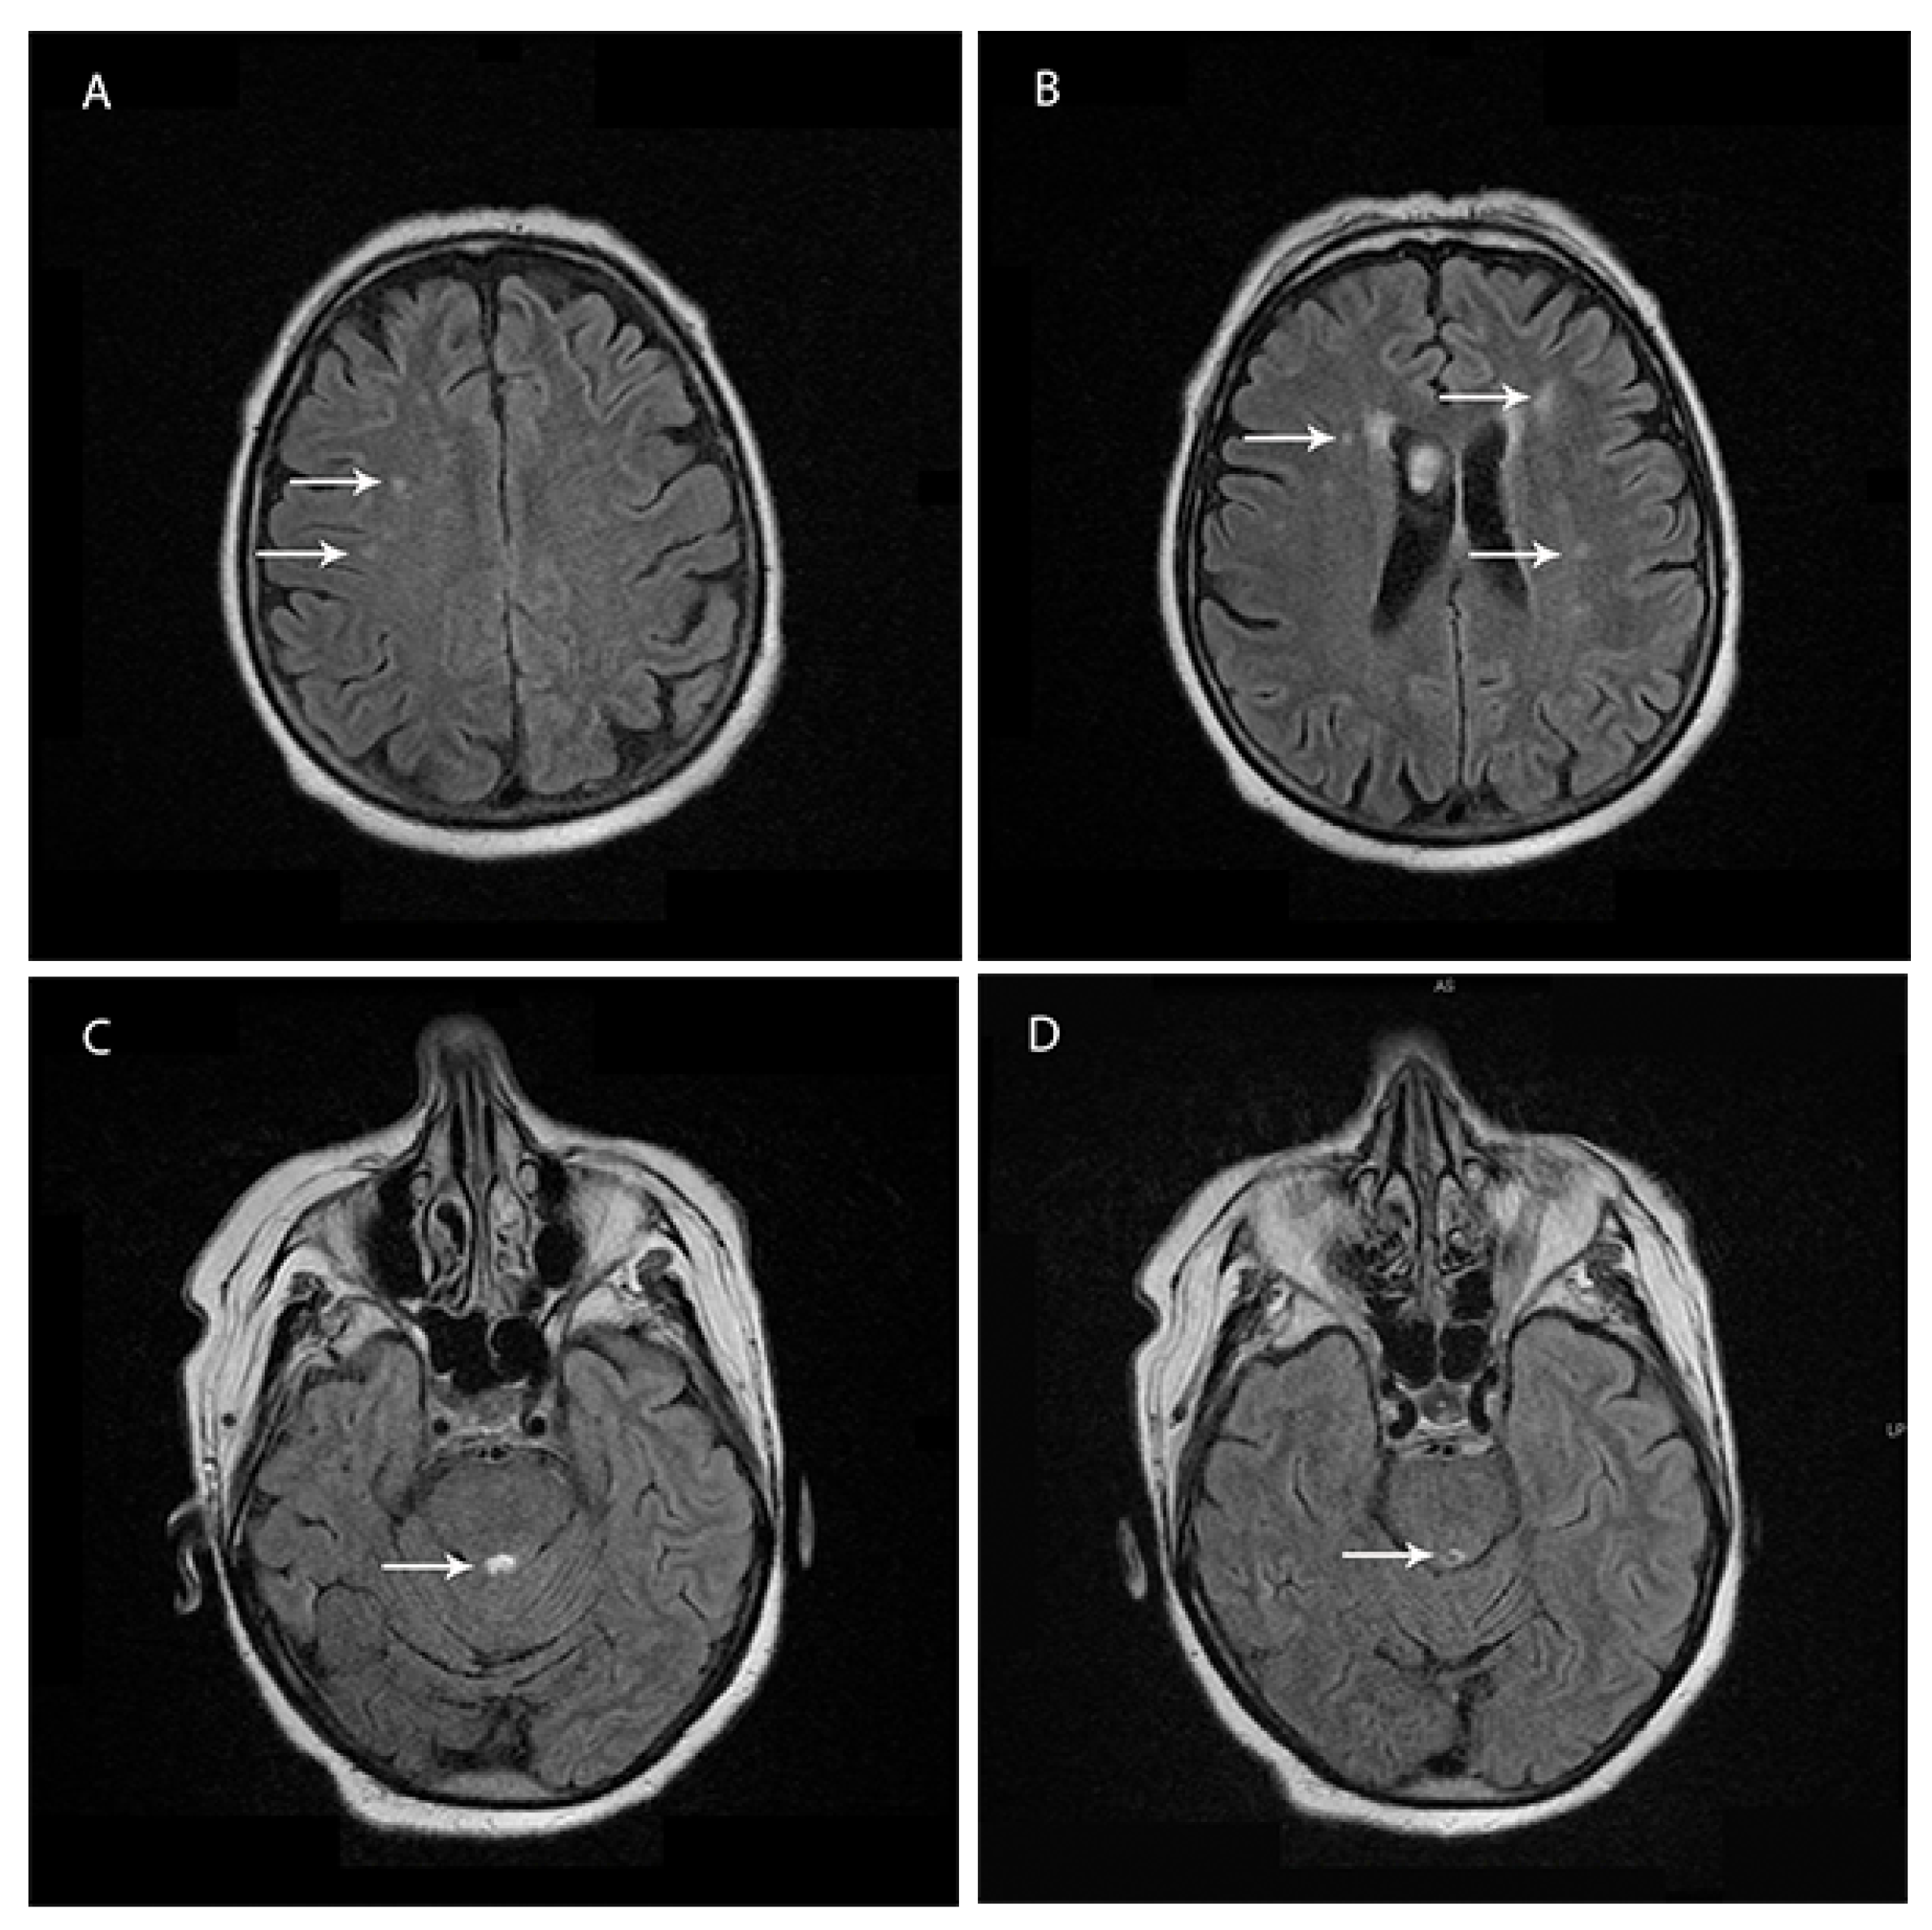

Brain magnetic resonance imaging (1.5 T MRI—11 February 2019) showed bilateral and patchy supratentorial subcortical increased signal intensities on T2-fluid attenuation-recovery (FLAIR) images in frontotemporal regions and a demyelinating lesion surrounding the Sylvian aqueduct (Figure 1A–D).

A high signal in caudate/putamen on magnetic resonance imaging (MRI) brain scan or at least two cortical regions (temporal, parietal, or occipital) either on diffusion-weighted imaging (DWI) or fluid-attenuated inversion recovery (FLAIR), represent characteristic findings in patients with CJD. Less frequently, periaqueductal grey matter hyperintensity in FLAIR images has been reported, which was present on the MRI of our patient [22,23]. In recent years, the DWI sequence was reported as the most sensitive in CJD, and often the cortical diffusion restriction is the first clue in CJD [24]. Moreover, the disease progression can also be monitored using the DWI sequence [25]. In our case, the DWI sequence was without pathological changes, but the MRI was performed early on during the disease. In this phase of the diagnostic route, our patient could be classified as “probable” CJD. Unfortunately, in the case of our patient, the MRI could not be repeated in the later stage of the disease due to technical issues, as the patient’s deteriorated clinical state made it too difficult to perform an MRI.

Figure 1. (AD) Brain magnetic resonance imaging (MRI) study on T2-fluid attenuation-recovery (FLAIR). (A,B) Bilateral supratentorial subcortical increased signal intensities on FLAIR images. (C,D) Periaqueductal grey matter hyperintensity in FLAIR images.